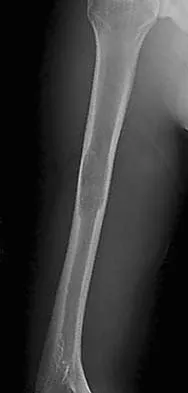

Figure 26a shows the radiograph of a 55-year-old woman who has pain in her right leg after falling. Laboratory studies reveal an elevated alkaline phosphatase level. A biopsy specimen from the proximal tibia is shown in Figure 26b. What is the most likely diagnosis?

Paget's disease of bone is a metabolic disorder of bone remodeling. The normally coupled process of bone resorption and deposition is lost, resulting in excessive localized bone resorption and compensatory increased bone formation. Pagetic bone tends to be more brittle; therefore, it is susceptible to pathologic fractures and subsequent deformities. Lander PH, Hadjipavlou AG: A dynamic classification of Paget's disease. J Bone Joint Surg Br 1986;68:431-438.